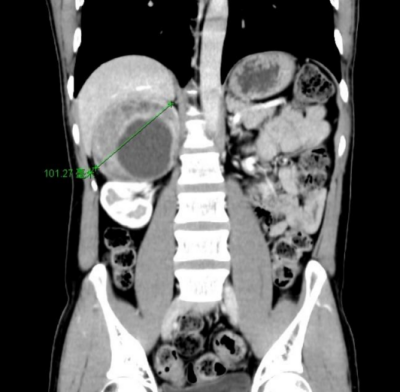

40岁的汤先生(化名)来自湖南娄底,近1年反复头晕、心悸,测血压经常高于180/110mmHg(标准血压收缩压<120mmHg、舒张压<80mmHg),有时高达230/120mmHg,长期使用降压药物却一直难以控制。经当地医院推荐,到香港马会app 就诊,CT检查后发现他右侧肾上腺有一个10cm*8cm巨大肿瘤。泌尿外科二区主任、主任医师刘玉明结合症状及CT影像结果,考虑为嗜铬细胞瘤。由于肿瘤体积巨大,与周围十二指肠、下腔静脉粘连紧密,需紧急手术治疗。

图1:CT示右侧肾上腺巨大肿瘤